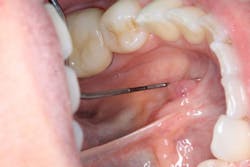

Figure 2: A view of the patient’s mass

Clinical assessment revealed a tissue-colored raised fluctuant mass on the left side of the lingual frenum, in the area of the submandibular gland duct. There was a slight tenderness to palpation with some firmness to the lesion overall. The mass measured approximately 4 mm by 5 mm in length (figures 1 and 2).